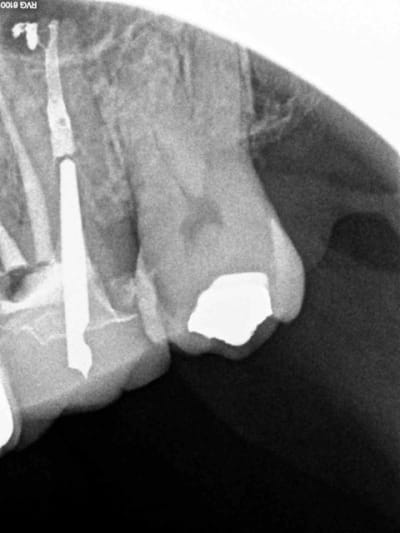

??? Dans ce cas ( moi meme) il n'a pas été utile de faire la remontée de gutta dans le palatin jusqu'à la chambre because tenon. Dans le MV2 par contre oui ( because pas de tenon).

Compris ?

Le mv1 et le dv ont été obturés il y a 8 ans en mono cone.

En gutta chaude la différence se voit car ca n'est pas homogène à la radio comparé à un monocone scellé.

Marc vas jouer du mac spadden sur le canal palatin si ca te chante, mais pas sur moi ! -)))

4 wgbx1x - Eugenol

3 b4nxvh - Eugenol

1 phwbbp - Eugenol

in vivo 3 ans à l'air libre, monocone scellé, pas de digue : il y a une pèche à l'apex ? non.